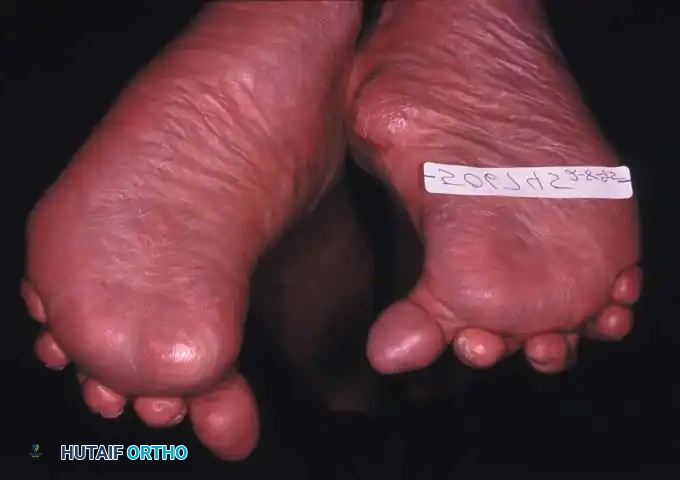

Fig. 81-1 Rheumatoid foot. Note the multiple severe deformities characteristic of rheumatoid arthritis of the forefoot, including advanced hallux valgus, subluxed and dislocated lesser metatarsophalangeal joints, claw toes, hammer toes, and prominent bursal formation.

Fig. 81-4 Multiple deformities of rheumatoid arthritis. Note the prominent bursa directly over the medial eminence and the severe dorsal posturing of the lesser digits.

Fig. 81-2 (A, B) Preoperative clinical views showing severe dorsal subluxation-dislocation of lesser toes. (C) Plantar view post-resection of metatarsal heads. (D) Excellent postoperative clinical alignment following first MTP arthrodesis and lesser metatarsal head excision.